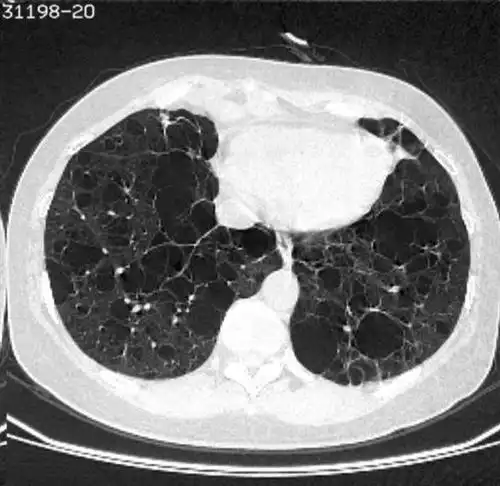

蜂窝肺